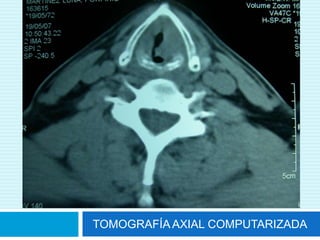

TOMOGRAFÍA AXIAL COMPUTARIZADA